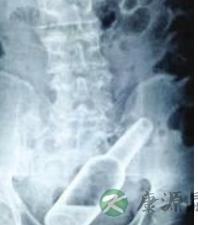

小编导读:通过腹部CT检查,在距离男孩肛门口7厘米的地方发现了一个拇指长、一圆硬币粗的完整玻璃瓶。

通过腹部CT检查,在距离男孩肛门口7厘米的地方发现了一个拇指长、一圆硬币粗的完整玻璃瓶。万一玻璃瓶破碎戳破肠道,后果就不堪设想了。考虑到瓶子距离肛门不远,四周光滑,陶艳娥决定试试灌肠。肠道在大量的生理盐水冲洗下,很快将玻璃瓶“冲”了出来。